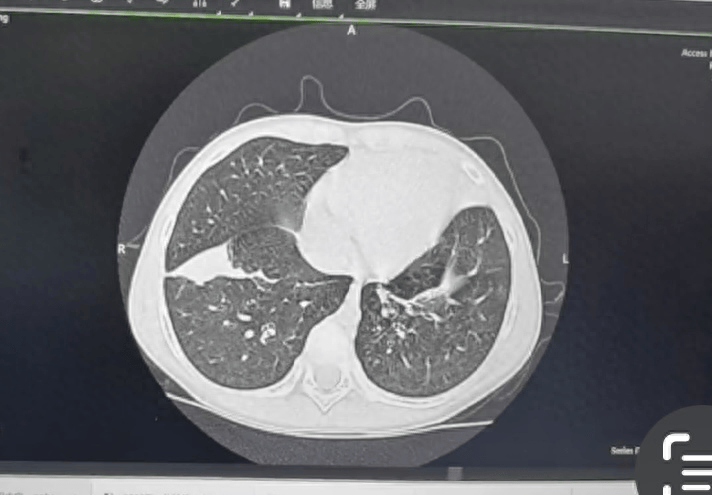

目前,支原体肺炎的诊断主要依靠支原体抗体检查和血清冷凝集试验以及鼻咽拭子的核酸检测。影像学表现是临床判断病情严重程度和评估预后的主要依据之一,肺炎支原体肺炎早期胸片或胸部CT主要表现为支气管血管周围纹理增粗、增多、支气管壁增厚,可有磨玻璃影、“树芽征”、小叶间隔增厚、网格影等,再结合上述检测即可作出诊断。

下面展示的是一组重症肺炎患儿经气管镜灌洗的前后变化,不难看出,灌洗后的肺部炎症,较之前明显吸收。

气管镜灌洗后